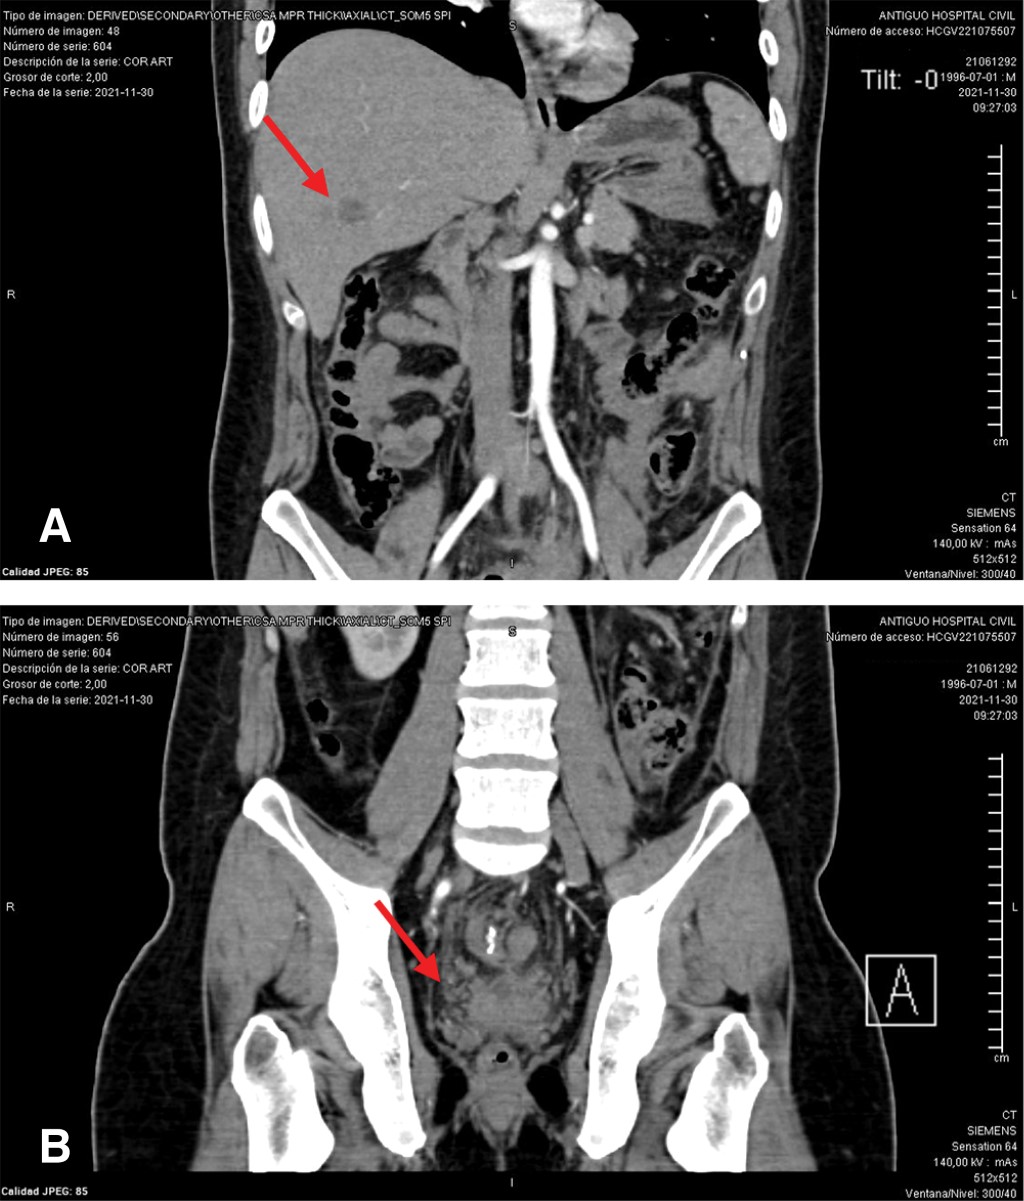

Introduction: rectal cancer can occur in young patients with no family history, so it is important to assess screening studies in the young population. Clinical case: 25-year-old male with no family history, goes to the emergency department due to a distal bowel obstruction with a history of 30 kg weight loss and diarrhea of six months' duration, imaging studies with an upper rectal lesion and secondary liver nodules. Discussion: results from studies worldwide support the benefits of changing the age of screening for colorectal cancer for patients of any age. The implementation of screening is intended to reduce mortality, but not incidence rates. Conclusions: it is necessary to take into account and assess the signs and symptoms of young patients who come to the consult with symptoms suggestive of a tumor and not wait for them to arrive at an emergency department with data of distal large intestine occlusion and think that cancer can be present also in young patients.

Figure 2

Figure 3